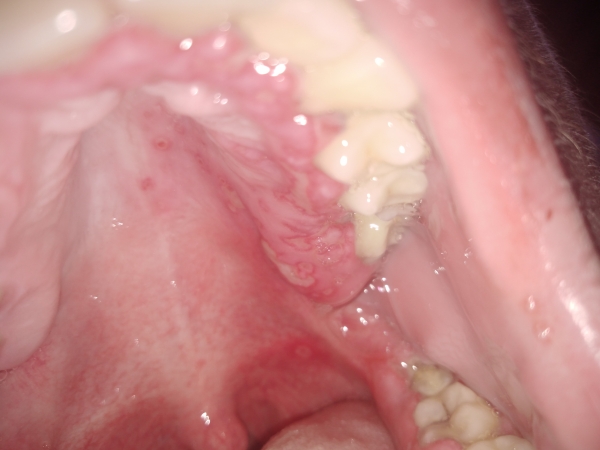

У меня прорезался зуб мудрости, и появились сопутствующие этому симптомы, такие как температура, воспаление гортани и гланд, плохой запах изо рта. Сходил к врачу, удалять зуб не стали, потому что растёт ровно. Прописали Хлоргексидин, Биглюконата и Супрастин. Не помогло. Воспаляться десна, а со стороны зуба мудрости, появились язвочки./p>